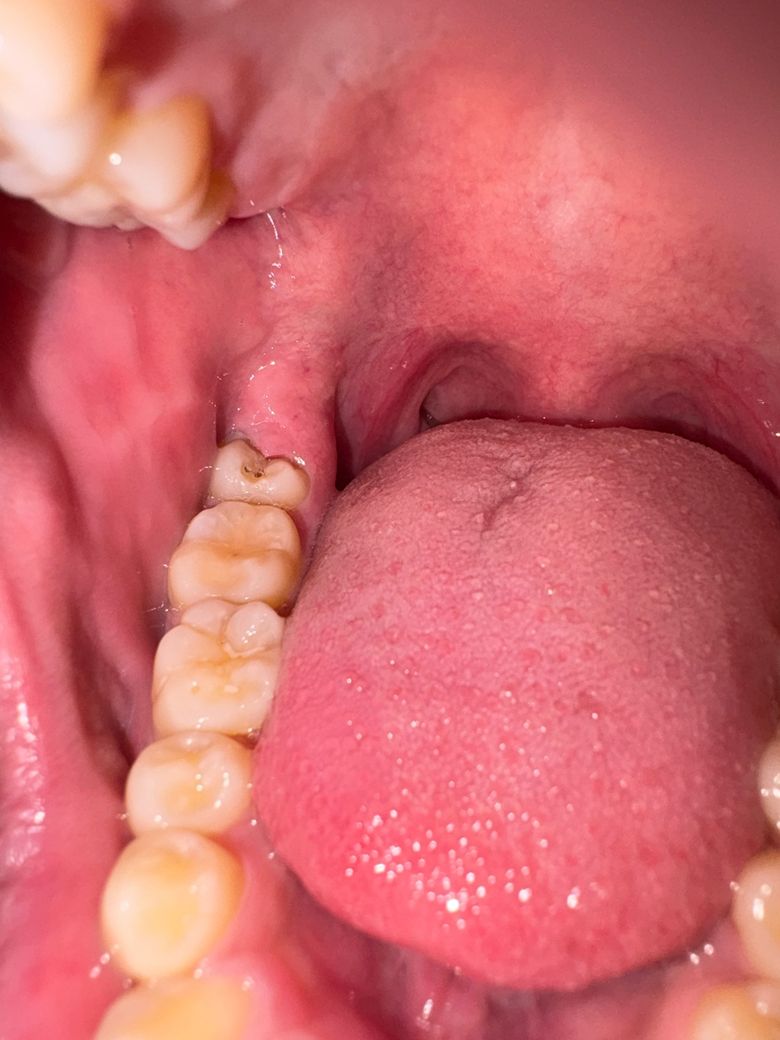

사랑니에 구멍이 생긴거 같아요 충치일까요

이거 사랑니에 충치 맞나요?

치간칫솔 뾰족한 부분으로 넣으면 구멍이 있어요

검은 부분도 명확하게 보입니다 통증은 없어요

1. 네 충치 명확합니다

2. 주변 잇몸도 부어 있네요 사랑니는 빼는게 좋겠습니다